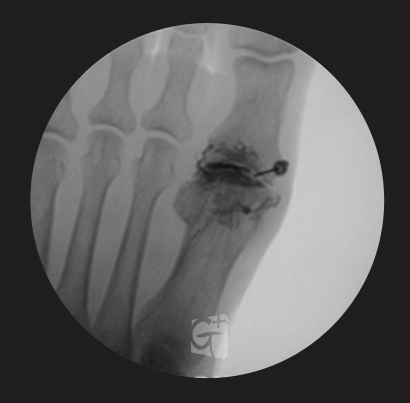

발가락 치료

발가락 관절염 등

염증 부위에 주사 시술 -